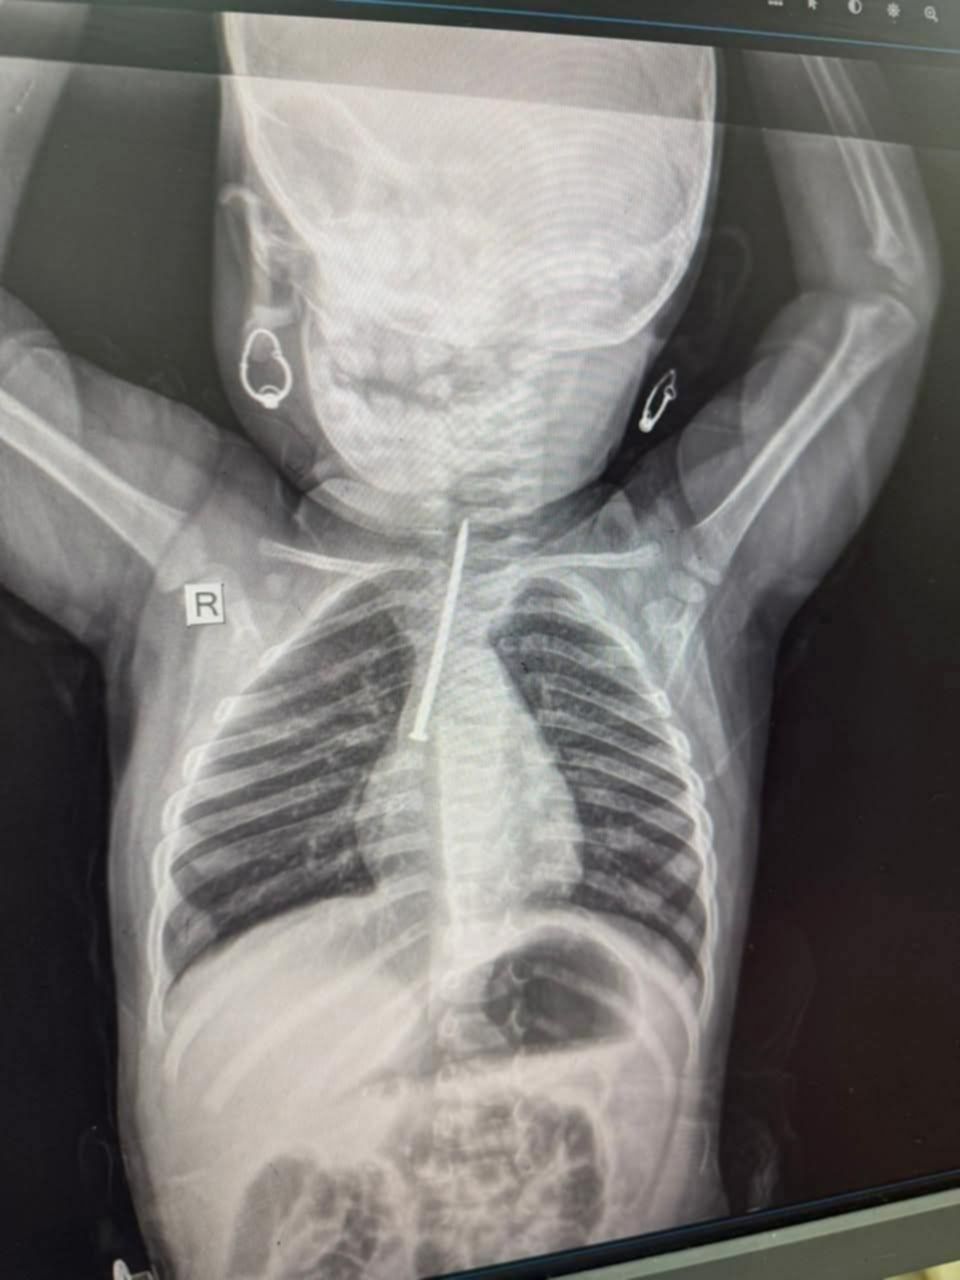

طفله في حوادث مستشفى كسلا تبلغ من العمر عشرة اشهر قامت بابتلاع مسمار و ثبت في القصبة الهوائية انظرو الى مسمار بهذا الطول ليهو ١٢ ساعة و حال اهلها من حال البلد ما يملكوا شي و عشمهم في ربنا ثم انتوا اهل الخير محتاجين ندفع لاجراء العملية مبلغ 300 الف

طفله في حوادث مستشفى كسلا تبلغ من العمر عشرة اشهر قامت بابتلاع مسمار و ثبت في ا…